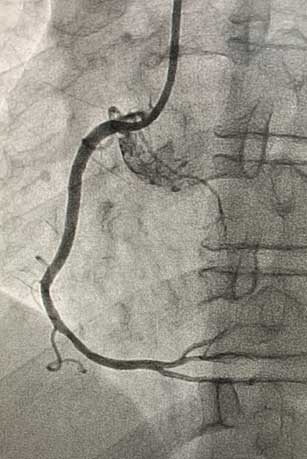

患者为45岁男性,因间断发作剑突下疼痛10天就诊于我院心血管内科门诊,完善检查后以“冠心病、不稳定型心绞痛”收入心血管内科病房。冠脉造影示:右冠近中段90%节段性狭窄,与冠脉CTA诊断一致。患者右冠状动脉近中段存在重度狭窄病变,有植入冠脉支架指征。心血管内科介入团队在赵慧强主任的带领下,针对此患者制定了个体化介入治疗方案:患者的病变特点为右冠状动脉近中段病变,无严重钙化、迂曲,非左主干病变、分叉病变、小血管病变,且患者年龄较轻,综合考虑远期预后效果,此患者适用于植入生物可吸收支架。冠脉介入团队进行了详细的术前讨论和充分的准备,经过患者同意后,为其行生物可吸收支架植入术。术中,经过充分预扩张处理右冠状动脉近中段狭窄病变后,成功于右冠状动脉病变处植入一枚生物可吸收支架。术后即刻复查冠脉造影:右冠状动脉中段支架膨胀贴壁良好,手术成功。

生物可吸收支架植入术前.jpg术前